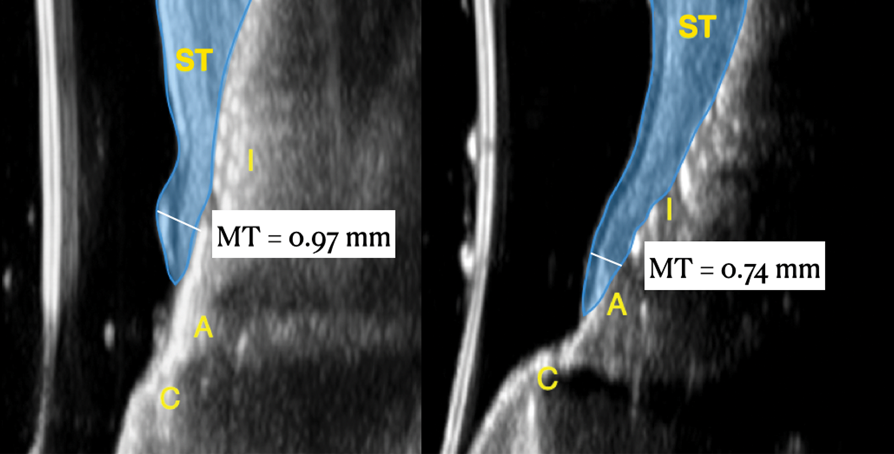

Fig 19. Ultrasonographic comparison of the volumetric gain obtained with the intervention. Fig 19: Baseline. Fig 20: 1-year post-treatment. “C” identifies the crown, “A” the abutment, “I” the implant fixture, and “ST” the soft tissue. The soft tissue at baseline (Fig 19) is highlighted in blue, while the soft tissue at the 1-year follow-up (Fig 20) is shown in purple. Mucosal thickness (“MT”) at baseline (Fig 19) and at 1 year (Fig 20) is also displayed. (In both figures, the left panel is implant No. 8 midfacial, and the right panel is implant No. 9 midfacial.)

Figure 19

Fig 20. Ultrasonographic comparison of the volumetric gain obtained with the intervention. Fig 19: Baseline. Fig 20: 1-year post-treatment. “C” identifies the crown, “A” the abutment, “I” the implant fixture, and “ST” the soft tissue. The soft tissue at baseline (Fig 19) is highlighted in blue, while the soft tissue at the 1-year follow-up (Fig 20) is shown in purple. Mucosal thickness (“MT”) at baseline (Fig 19) and at 1 year (Fig 20) is also displayed. (In both figures, the left panel is implant No. 8 midfacial, and the right panel is implant No. 9 midfacial.)

Figure 20

Ultrasonographic Assessment of Mucosal Thickness Gain

Previous studies have described in detail the ultrasound equipment setup and scanning procedures.7,13,15,16 A commercially available ultrasound imaging devicewas used with a 24-MHz miniature-sized transducer to obtain midfacial and interproximal scans at baseline and at 1-year follow-up. The transducer was oriented perpendicular to the occlusal plane and parallel to the implant's long axis to generate "B-mode" grayscale images. B-mode generates 2-dimensional grayscale images in which brightness is the result of the returned echo signal and its strength, which is dependent on the acoustical properties of the periodontal hard- and soft-tissue structures. The scans were saved in digital imaging and communications in medicine (DICOM) files and later exported into a software package, where mucosal thickness was measured 1.5 mm apical to the soft-tissue margin and found to be 0.97 mm and 0.74 mm at the right and left implants, respectively. After 12 months, the respective mucosal thickness was 2.75 mm and 2.48 mm. The soft-tissue thickness gain at the level of the right implant was 1.78 mm for the right implant, and 1.74 mm for the left implant.

This article has described the use of real-time, non-ionizing, high-frequency ultrasonography for assessing the increase in soft-tissue thickness and the anatomy of the peri-implant structures pretreatment and at the 1-year follow-up. The reliability and reproducibility of this technology has been shown in several clinical studies in which ultrasonography also was utilized to assess tissue perfusion after graft procedures and the levels of blood flow at healthy versus diseased implant sites.7,13,15,16,26,27 Ultrasonography enabled the observation of a substantial gain of mucosal thickness at 1 year, with the initial soft tissue (measured 1.5 mm apical to the soft-tissue margin) being 0.97 mm and 0.74 mm at the right and left dental implants, respectively, while the final mucosal thickness was 2.75 mm and 2.48 mm at the right and left dental implants, respectively. Considerable evidence supports the key role augmented gingival thickness plays in the stability of the soft-tissue margin in natural dentition,17,28 and it is reasonable to assume that this concept also may be valid at implant sites.13 The benefits of soft-tissue phenotype modification, in terms of increased keratinized mucosa and mucosal thickness, also include patient-reported outcomes and implant health-related parameters.29